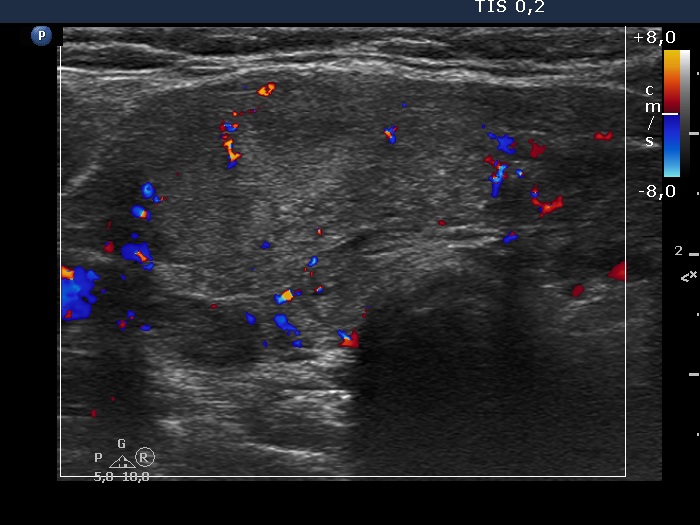

Consecutive patients with the final diagnosis of Hashimoto's thyroiditis - case 57 (774) (ultrasonographic picture 7)

Isthmus, transverse view, color Doppler mode. The vascularization is non-specific.